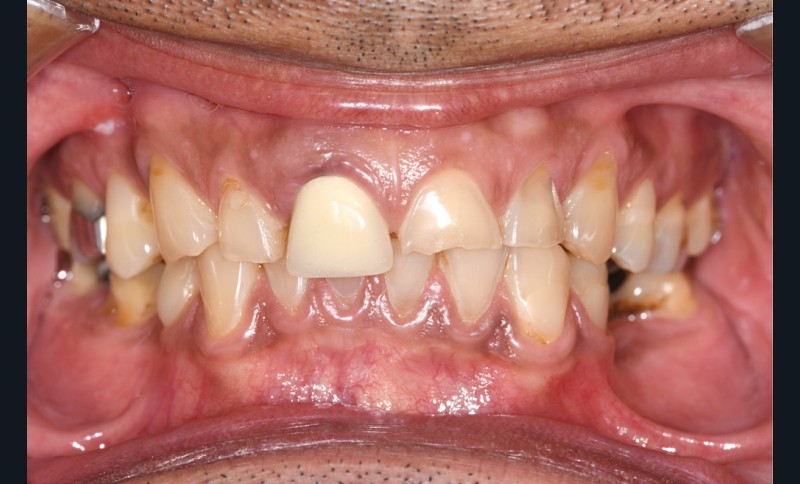

L’usure dentaire est de plus en plus fréquente au sein de nos cabinets. Nos patients y sont sujets de par leur alimentation parfois plus acide, leur mode de vie souvent plus stressant, et également une hygiène qui s’améliore et des dents qui vieillissent davantage.

L’étiologie de cette usure est multifactorielle, revêtant une composante de type attrition (usure par contact dento-

dentaire), une composante abrasive avec un brossage traumatique et, en dernier lieu, une légère composante tribo-érosive de par une pratique importante de sport avec gel et boisson acide (fig. 1-4) [1].